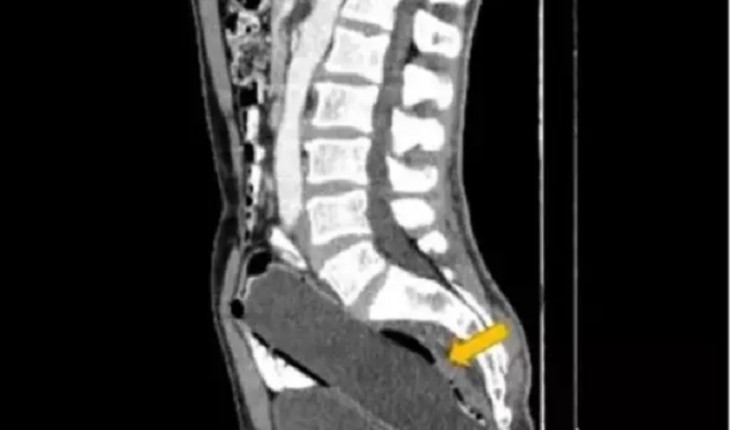

Com fortes dores nas costas, Nathalie Moellhausen precisou ser atendida às pressas; equipe da atleta revelou seu diagnóstico.

Esgrimista Nathalie Moellhausen é eliminada das Olimpíadas após sentir fortes dores; ela foi socorrida às pressas.